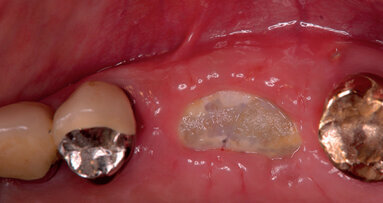

- Ripristinare un difetto osseo (Figg. 1-3).

- Preservazione del capitale tessutale (chirurgia pre-implantare anticipata) (Figg. 4-10).